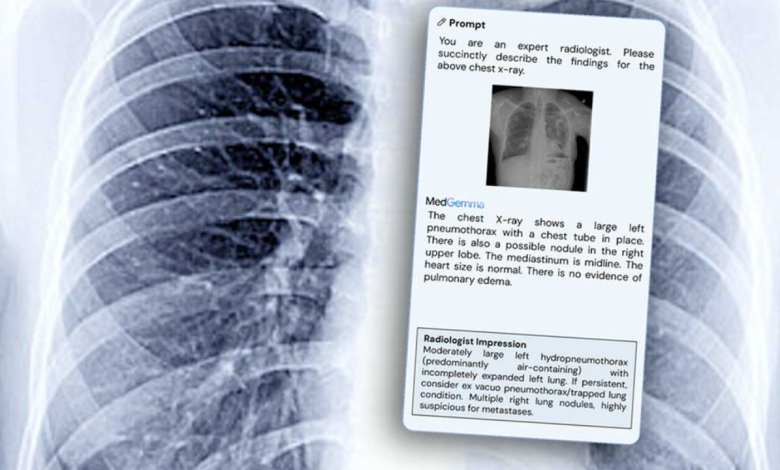

Google AI: హెల్త్కేర్ సెక్టార్లో గూగుల్ ఇప్పుడు ఏకంగా టాప్ ప్లేస్కి దూసుకువచ్చింది. ఓ రేంజ్ ఆవిష్కరణతో, అది కూడా ఫ్రీగా రావడంతో.. మెడ్గిమ్మా( MedGemma) ఇప్పుడు మార్కెట్ను షేక్ చేస్తోంది. . ఇది నెక్స్ట్-జెన్ AI మోడల్. చెస్ట్ ఎక్స్-రేలు, మెడికల్ పిక్చర్స్, పేషెంట్ హిస్టరీలను ఒక ట్రైన్డ్ రేడియాలజిస్ట్ ఎంత కరెక్టుగా అనలైజ్ చేస్తారో,ఇప్పుడు ఇది కూడా అంతే పవర్ఫుల్గా ఇది చేయగలదు. దీని బిగ్గెస్ట్ పాయింట్ ఏంటంటే, ఇది ఓపెన్-సోర్స్, ఎవరైనా యూజ్ చేసుకోవచ్చు. అందుకే గూగుల్ ఈ మూవ్తో AI హెల్త్కేర్ లీడర్గా నిలుస్తోందంటున్నారు నిపుణులు.

Google AI: రీసెంట్గా లాంచ్ అయిన మెడ్గిమ్మా( MedGemma) 27B మెడికల్ AIలో గోల్డ్ స్టాండర్డ్ అయిన MedQA బెంచ్మార్క్లో సూపర్ ఇంప్రెసివ్గా 87.7% స్కోర్ చేసింది. ఈవెన్ దీని స్మాల్ వెర్షన్ కూడా 81% యాక్యూరసీతో యూఎస్ రేడియాలజిస్టుల నుంచి వాలిడేషన్ పొందింది. ఇది రియల్-వరల్డ్ పేషెంట్ కేర్లో అసిస్ట్ చేయడానికి మోర్ దెన్ ఎనఫ్! గూగుల్ AI పవర్ ఎంత స్ట్రాంగ్ ఉందో ఈ రిజల్ట్స్తో క్లియర్గా కనిపిస్తోంది.

ఈ మోడల్స్ విజువల్స్తో పాటు టెక్స్ట్ని కూడా అండర్స్టాండ్ చేసుకునేలా బిల్డ్ చేశారు. కాబట్టి MedGemma కేవలం ఎక్స్-రేను స్కాన్ చేయడమే కాదు, పేషెంట్ హిస్టరీ లేదా డాక్టర్ నోట్స్ని కూడా ఇంటర్ప్రెట్ చేయగలదు. ఇది క్లినిషియన్స్కి ఓ పవర్ఫుల్ డిజిటల్ సెకండ్ ఒపీనియన్ లాంటిది.